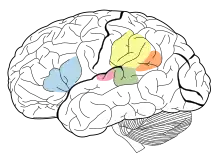

Menneskesprog har de lingvistiske egenskaber produktivitet og displacement, og afhænger fuldstændigt af sociale konventioner og indlæring. Deres komplekse struktur muliggør en langt bredere vifte af udtryk end noget kendt system af dyrs kommunikation. Sprog menes at have oprindelse i, da tidlige abemennesker gradvist begyndte at ændre deres primat-kommunikationssystemer, udviklede indlevelsesevne (ofte kaldet Theory of Mind) og en delt intentionalitet.[5][6] Denne udvikling tænkes at være sket samtidigt med en forøgelse af hjernevolumen, og mange lingvister anser sprogets strukturer for at være udviklet til specifikke kommunikative og sociale funktioner. Sprog bearbejdes i mange dele af hjernen, men især i Brocas og Wernickes område. Mennesker udvikler sproget gennem social interaktion i den tidlige barndom, og børn taler normalt flydende, når de er tre år gamle. Brugen af sprog er dybt forankret i menneskers kultur, og derfor har det udover sin strengt kommunikative anvendelse mange sociale og kulturelle betydninger som en indikator på identitet, social stratificering og til social pleje og underholdning.

Tidlige studier indenfor neurolingvistik involverede studier af sproget hos mennesker med hjernelæsioner for at se, hvordan læsioner i specifikke områder påvirker sprog og tale. På denne måde opdagede neurovidenskabsmænd i det 19. århundrede, at to områder af hjernen er centrale for den kognitive behandling af sprog. Det første område, Wernickes område, er i den bageste del af gyrus temporalis superior. Personer med en læsion i denne del af hjernen udvikler impressiv afasi, en tilstand hvor der er en væsentlig svækkelse af sprogforståelse, mens tale beholder en naturligt-lydende rytme og en relativt normal sætningsstruktur. Det andet område er Brocas område i den bageste del af gyrus frontalis inferior. Personer med en læsion i dette område udvikler ekspressiv afasi, en tilstand hvor de ved hvad det er de vil sige, men blot ikke kan få det udtrykt.[57] De er typisk i stand til at forstå, hvad der bliver sagt til dem, men er ude af stand til at tale flydende. Der kan også være andre symptomer ved ekspressiv afasi, heriblandt problemer med talegentagelse. Tilstanden påvirker både talt og skrevet sprog. De med denne type afasi udviser også ugrammatisk tale og manglende evne til at anvende syntaktisk information til at afgøre sætningers betydning. Både ekspressiv og impressiv afasi påvirker også brugen af tegnsprog på måder, der er sammenlignelig med, hvordan de påvirker tale, så at ekspressiv afasi får personen til at anvende tegn langsomt og med forkert grammatik, mens impressiv afasi får personen til at anvende tegn flydende, men uden at give mening for andre, og uden selv at kunne forstå andres tegn. Dette viser at svækkelsen specifikt vedrører evnen til at anvende sprog, og ikke fysiologien til produktion af tale.[58][59]